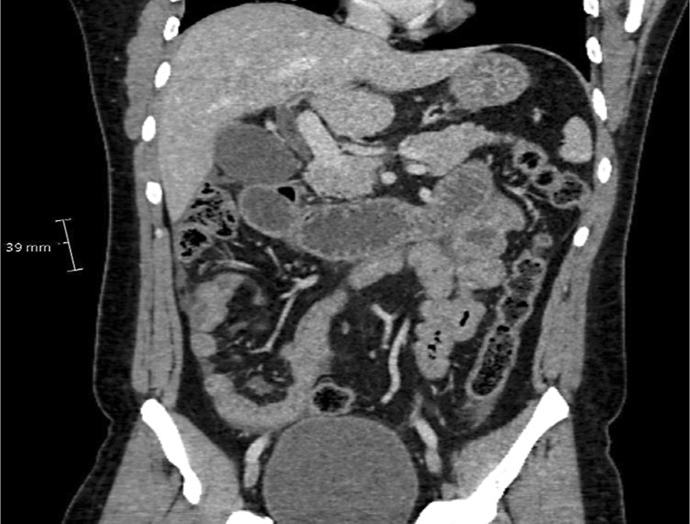

Case presentation: This case report presents a challenging case of a young man presenting with symptoms of abdominal pain, nausea, vomiting and non-specific symptoms of lethargy and fatigue. The case describes overlapping features with granulomatosis with polyangiitis (GPA) and anti-neutrophil cytoplasmic antibodies (ANCA)-positive and -negative vasculitis. The patient needed extensive workup and investigations to be eventually diagnosed with EGPA. In this case, myeloperoxidase (MPO) ANCA was negative, which is positive in the majority of EGPA cases, and this poses an additional diagnostic dilemma.